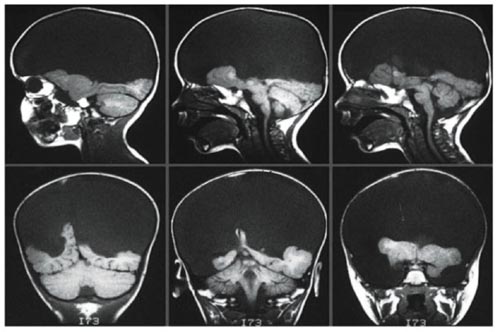

.jpg) 무뇌수두증 환자의 MRI사진. 대뇌 부분이 없어 검은색으로 나타난다

지난해 스웨덴의 뇌과학자 비요른 메르케르Bjorn Merker의 연구논문 발표 이후 뇌간과 의식의 관계에 대한 논쟁이 뜨거워지고 있다. 우리들은 그간 대뇌피질이 없으면 생각할 수도 없고 인간적인 행동을 할 수도 없다고 생각해왔다. 그러나 그의 연구 결과에 의하면 뇌간만 남은 무뇌수두증 환자라도 사람을 알아보고 감정을 표현한다. 비록 시각에 결함이 있고 말을 못하지만 주변에서 벌어지는 일들을 알아채고 웃음을 지으며, 즐거운 노래에는 행복해하고 슬픈 노래에는 우울해한다. 주목할 점은 그들의 행동이 동물적이기보다 인간만의 특성을 보여준다는 것이다.